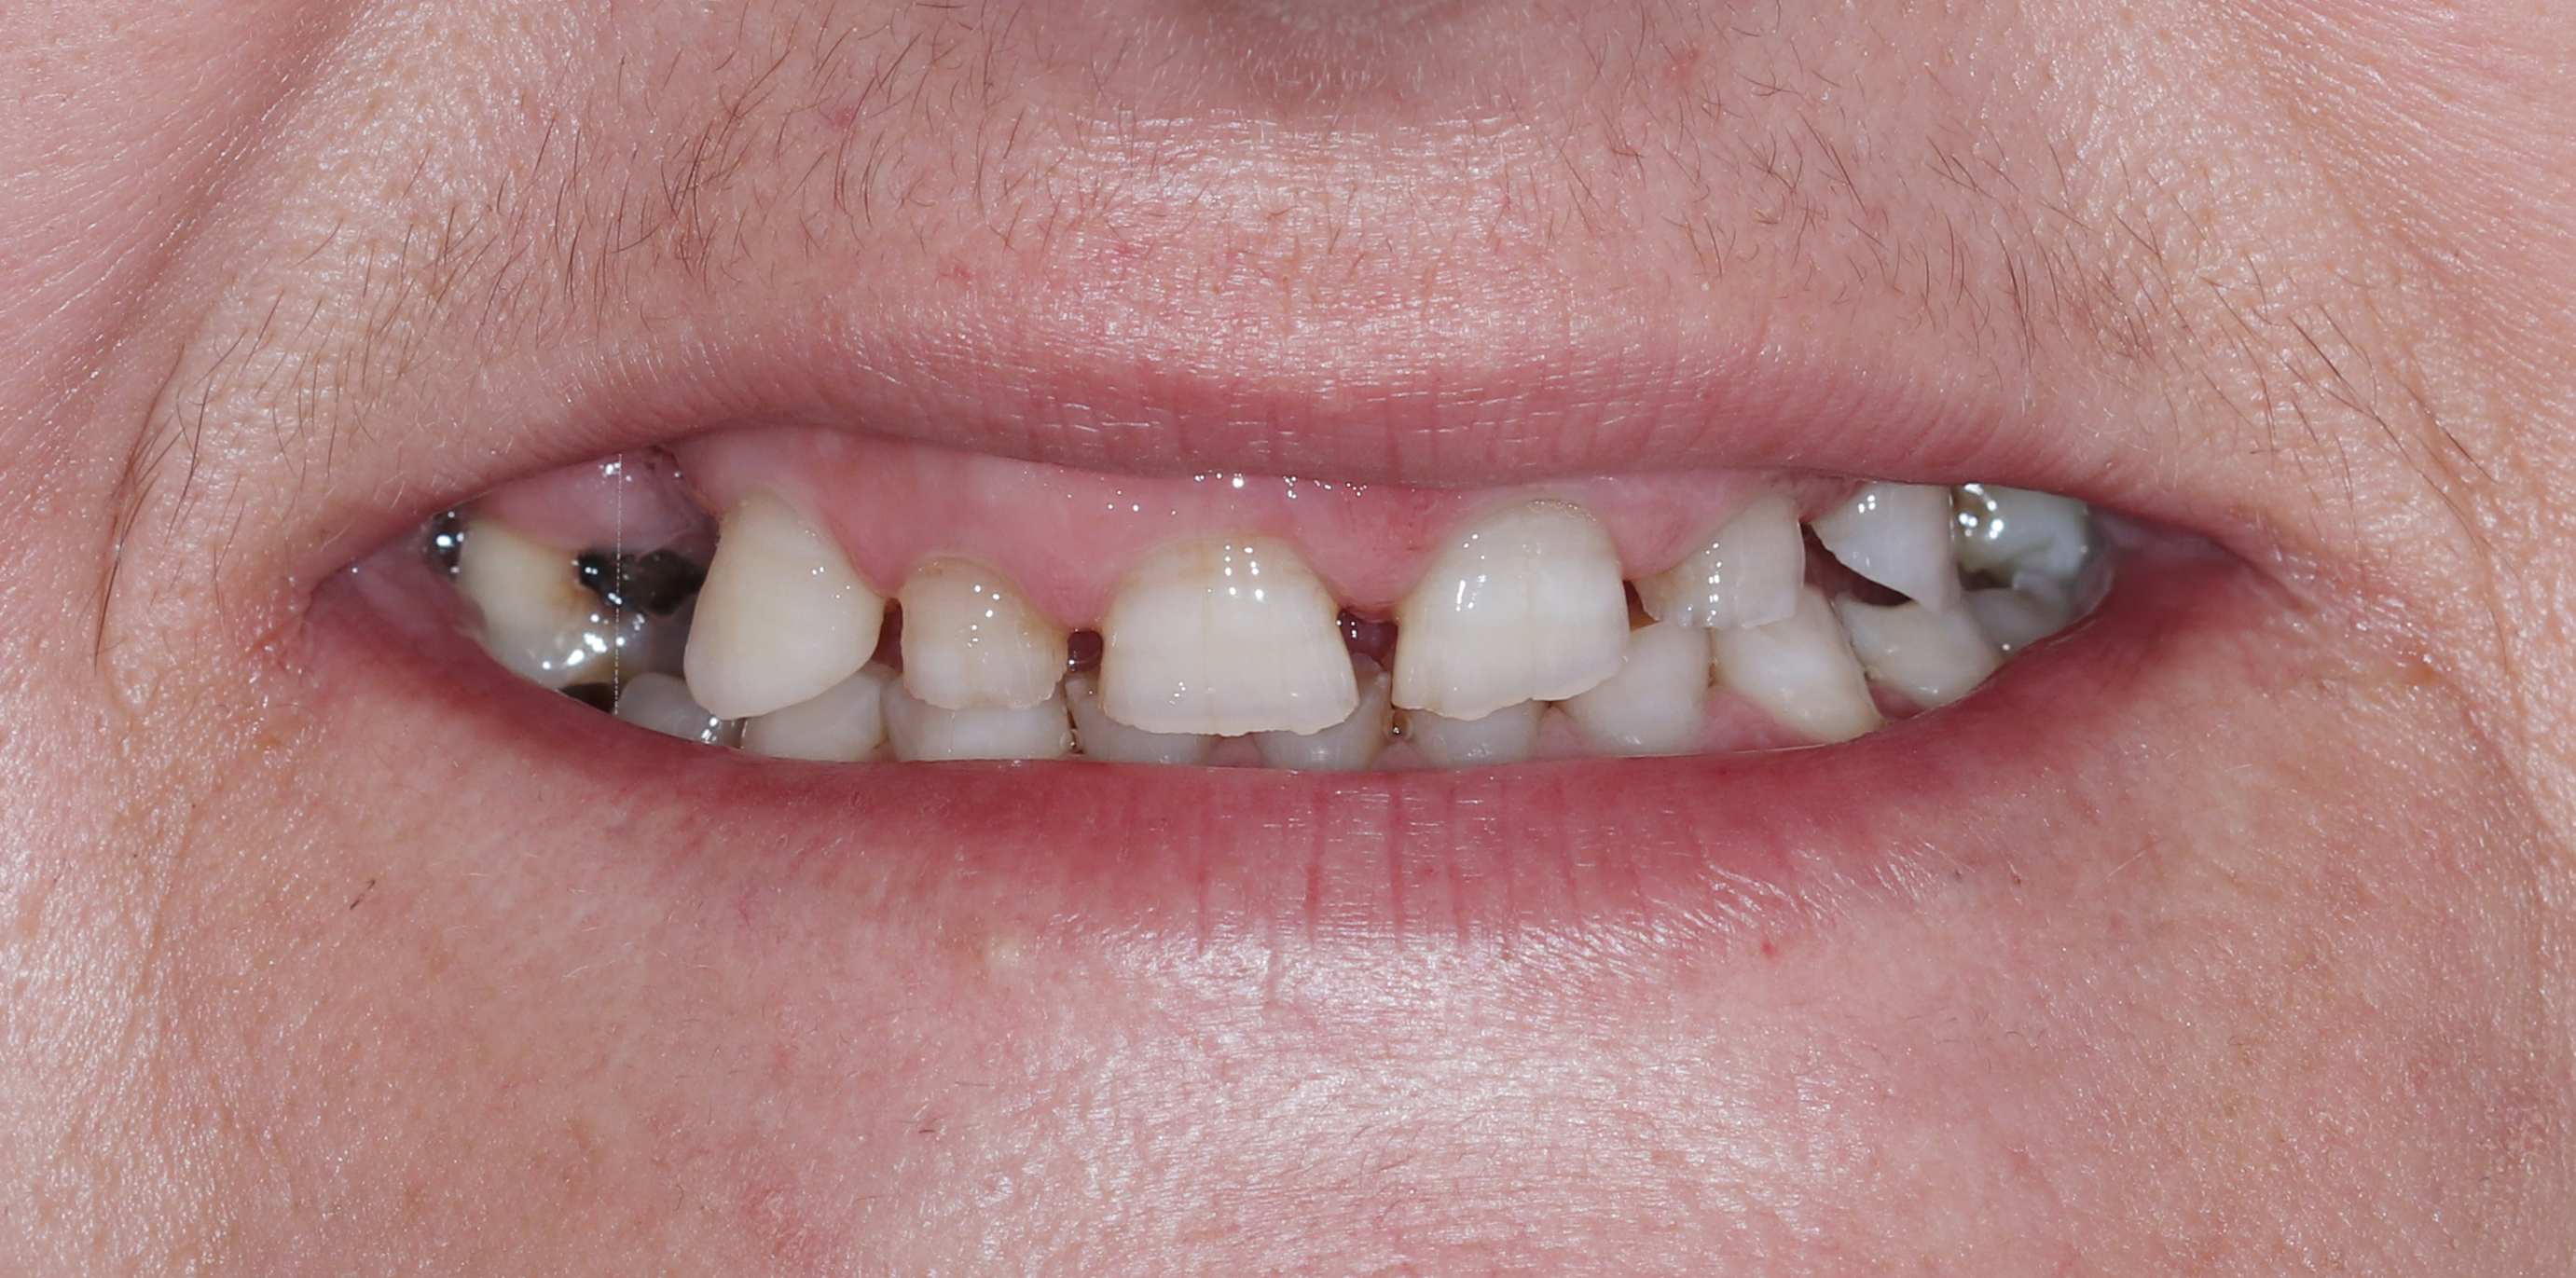

Ασθενής με αποδιοργανωμένη, εκτενώς φθαρμένη οδοντοφυΐα, τερηδόνες και κατεστραμμένα δόντια στην άνω γνάθο που προκαλούσαν έντονους πόνους, προσήλθε στο Aesthetic Dental Studio στην Καλαμάτα με στόχο την αισθητική και λειτουργική αποκατάσταση του στόματός της.

Σε πρώτη φάση, αφαιρέθηκαν τα δόντια που ήταν πλήρως κατεστραμμένα, πραγματοποιήθηκαν ενδοδοντικές θεραπείες στα δόντια που μπορούσαν να αποκατασταθούν και έγιναν εμφράξεις σε δόντια με απλή τερηδόνα. Έτσι, το στόμα σταθεροποιήθηκε και ήταν πλέον έτοιμο για την δεύτερη φάση της θεραπείας, που περιελάμβανε την προσθετική αποκατάσταση των δοντιών.